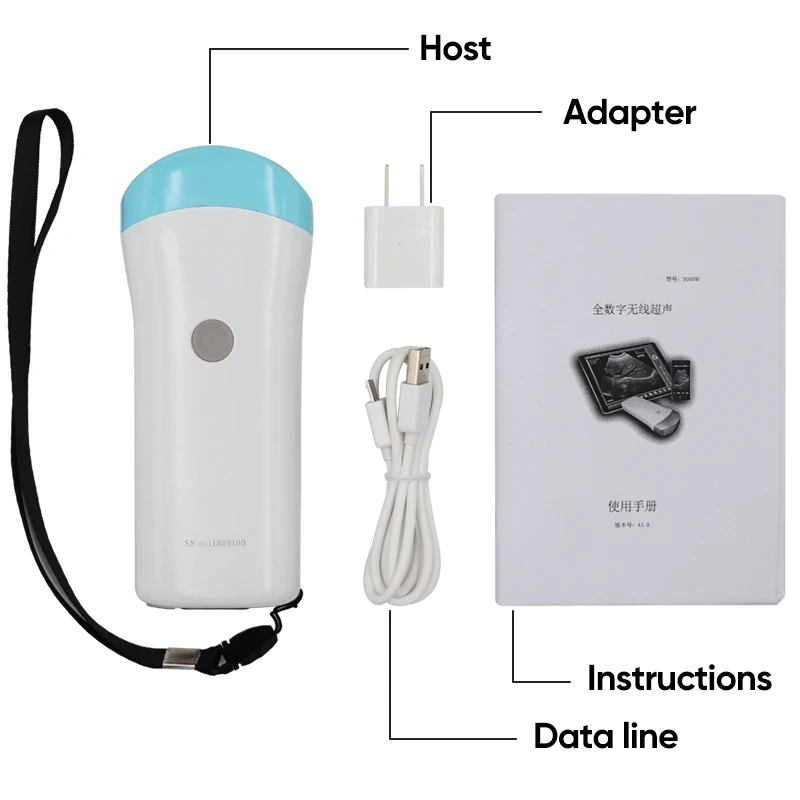

Standard Configuration:

-Main Host(probe) 1 Unit

-Internal Battery and charger 1 Set

-Non-slip lanyard

Convex Probe Pictures:

Linear Probe Pictures: